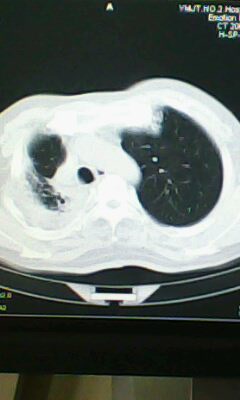

标题: CT25675:男 71 肺癌部分切除术后 3年 [打印本页]

标题: CT25675:男 71 肺癌部分切除术后 3年

两肺感染性病变,右侧肺膨胀不全,左侧上叶结节影及左侧颈部淋巴结肿大建议复查。

1)两肺感染性病变。2)右侧胸膜增厚。3)冠状动脉及主动脉钙化。

右肺癌切除术后。

右肺炎症,左肺炎症。

右侧胸膜肥厚。

1.右肺符合肿瘤切除术后ct表现。

2.左肺炎症。

术后改变,双肺内纤维索条影考虑与放疗有关。